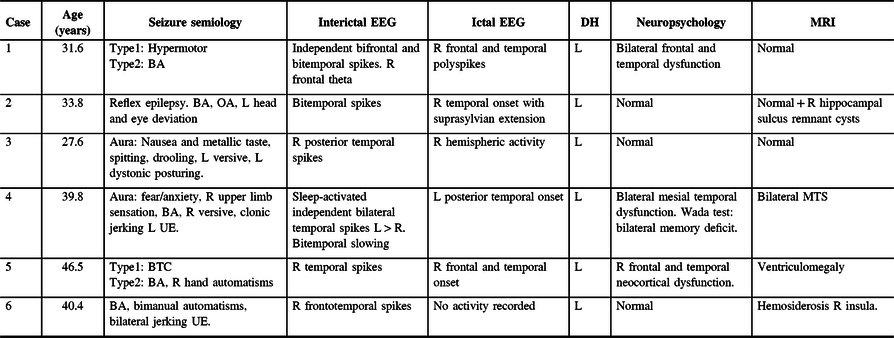

Of the 88 patients that had surgery following SEEG investigation, 6 cases were identified as TPE, representing 6.8% of all surgical cases. Five cases were right-sided TPE and one case was left-sided. Median age at the time of the surgery was 37 years (IQR = 31–42) and median duration of epilepsy was 16 years (IQR = 12–41). Three cases were non-lesional and three were lesional. Mean follow-up time after surgery was 2.7 years (SD ± 1.7). Noninvasive electroclinical findings, neuropsychology, and neuroimaging are shown in Table 1. Three patients had subdural electrodes investigation prior or in addition to SEEG. All patients underwent standard ATL and additional resections during the same procedure or subsequent surgery. All patients were seizure-free at their last follow-up appointment. Three patients were classified as Engel Ia, two patients experienced postoperative auras (Engel Ib), and one patient had scarce postoperative seizures that remitted spontaneously, being seizure-free for most of the follow-up time (Engel Ic). Table 2 summarizes invasive findings and surgical resections with postoperative outcomes. Pathology was consistent with either gliosis and or nonspecific changes in all cases for all resected tissue submitted for histopathology. Illustrations for each resection are shown in Figure 1A–F. A brief description of the six cases is shown below:

Table 1: Noninvasive studies: clinical features (seizure type, onset, and most prominent features), interictal and ictal EEG findings, neuropsychological testing, and MRI

BA = behavioral arrest; BTC = bilateral tonic-clonic seizures or secondary generalization; DH = dominant hemisphere (language lateralization); GTC = generalized tonic-clonic seizures; IQ = intellectual quotient; L = left; MTS = Mesial temporal sclerosis; OA = oral automatisms; R = right; UE = upper extremity.

Seizure classification according to ILAE 2017.

Table 2: Summary of invasive studies and surgical resections

Am = amygdala; AH = anterior hippocampus; ATL = Anterior temporal lobectomy; Engel class = Engel classification; H = hippocampus; L = left; LVFA = low-voltage fast activity; PH = posterior hippocampus; R = right; SEEG = stereo-encephalography.